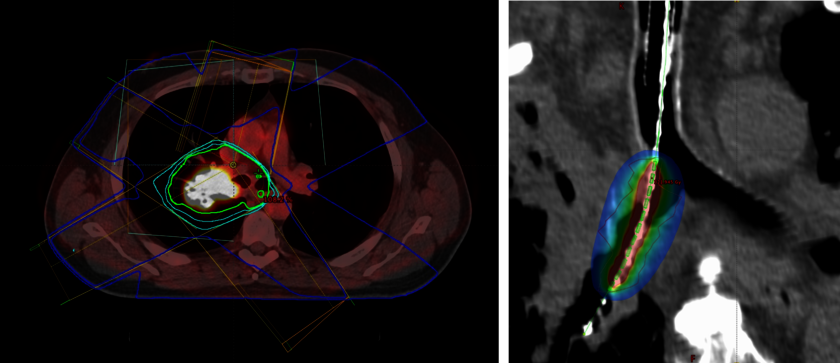

Lungenkrebs

links: Bestrahlungsplan eines Lungenkrebses mit PET-CT.

rechts: Bestrahlungsplan Brachytherapie im rechten Hauptbronchus.

Für die Behandlung von Patienten mit Lungenkrebs steht neben den üblichen strahlentherapeutischen Verfahren am Linearbeschleuniger auch die Möglichkeit einer Bestrahlung von innen mit radioaktivem Strahler(Brachytherapie) zur Verfügung.